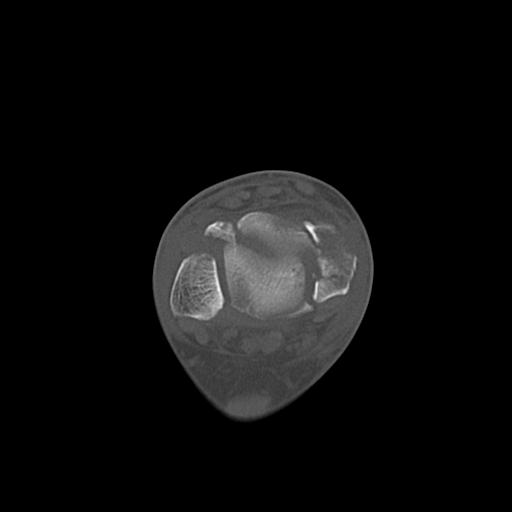

49554 3/13 膝 4R 3/16 4R 1/18 2R 78歳男性 膝蓋骨骨折